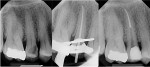

The simple and logical progression of the Basic and Advanced ESX instrumentation protocols is a product of the superior manufacturing quality of the established EndoSequence File, along with the addition of two new features: advanced BT-Tip Technology and a new, logical, and safe Single Stroke and Clean operator motion that makes the new ESX File System both efficient and simple for clinicians performing root canal therapy with basic or advanced protocol (Figure 5 and Figure 6).